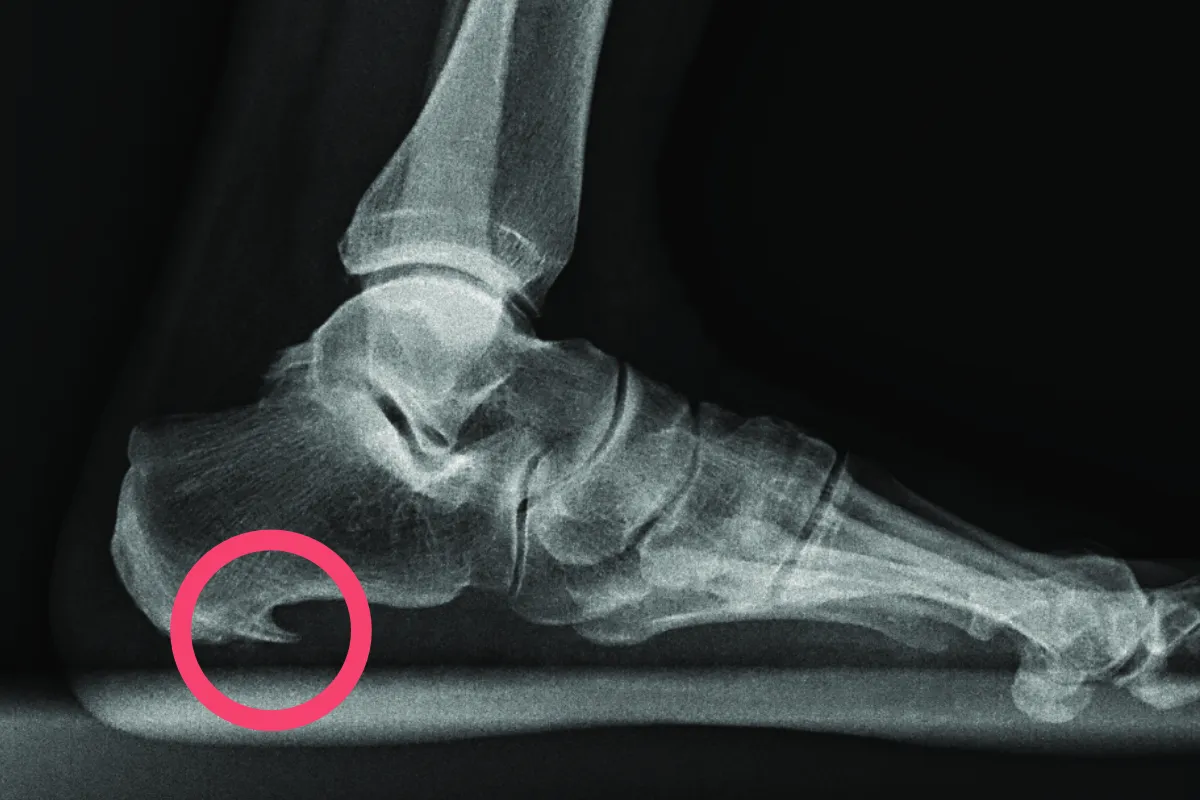

Właściwa diagnoza jest tu absolutnie kluczowa. Zawsze powtarzam moim pacjentom, że bez wizyty u ortopedy nie ma mowy o skutecznym leczeniu. Lekarz postawi diagnozę na podstawie badania klinicznego, podczas którego ucisk na odpowiednie punkty na pięcie wywoła ból. Potwierdzeniem może być zdjęcie rentgenowskie (RTG), które pokaże ewentualne zwapnienia w okolicy przyczepu rozcięgna, lub badanie ultrasonograficzne (USG), które pozwoli ocenić stan samego rozcięgna i otaczających tkanek.